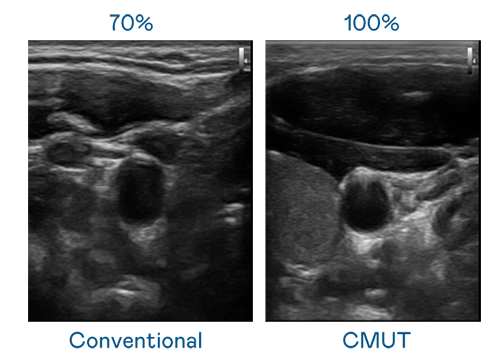

CMUT 技术是一种用电容式微机电元件来产生超音波讯号的技术。与传统 PZT 压电式技术相比,CMUT 频宽增加 30%,更宽频的超音波讯号让影像解析度大幅提升,是实现高影像品质医疗超音波扫描、促进精准医疗发展的关键技术。

超音波影像的解析度高低,首先取决于探头能发出的讯号频宽。AG百家乐 CMUT 可提供高清晰的超音波讯号,提供高频宽、高灵敏度、影像纹理细节更高的超音波影像,协助医护人员缩短影像判读时间及利用精准的医疗影像进行诊断。